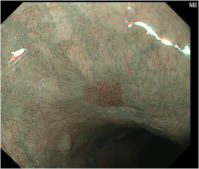

NBIによる食道の観察像例

NBIと拡大機能を併用した

食道の観察像例